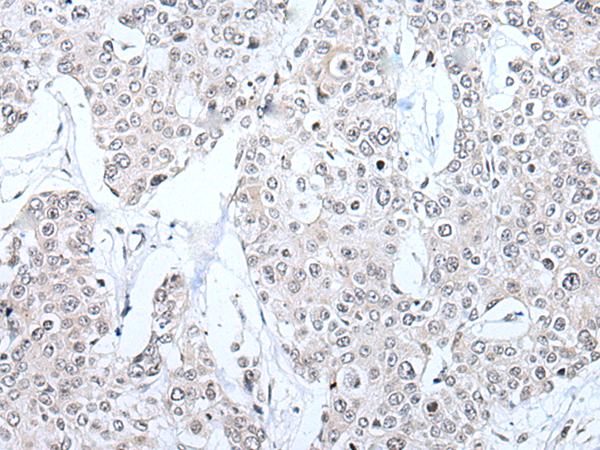

IHC positive control: |

Human esophagus cancer and human prostate cancer |